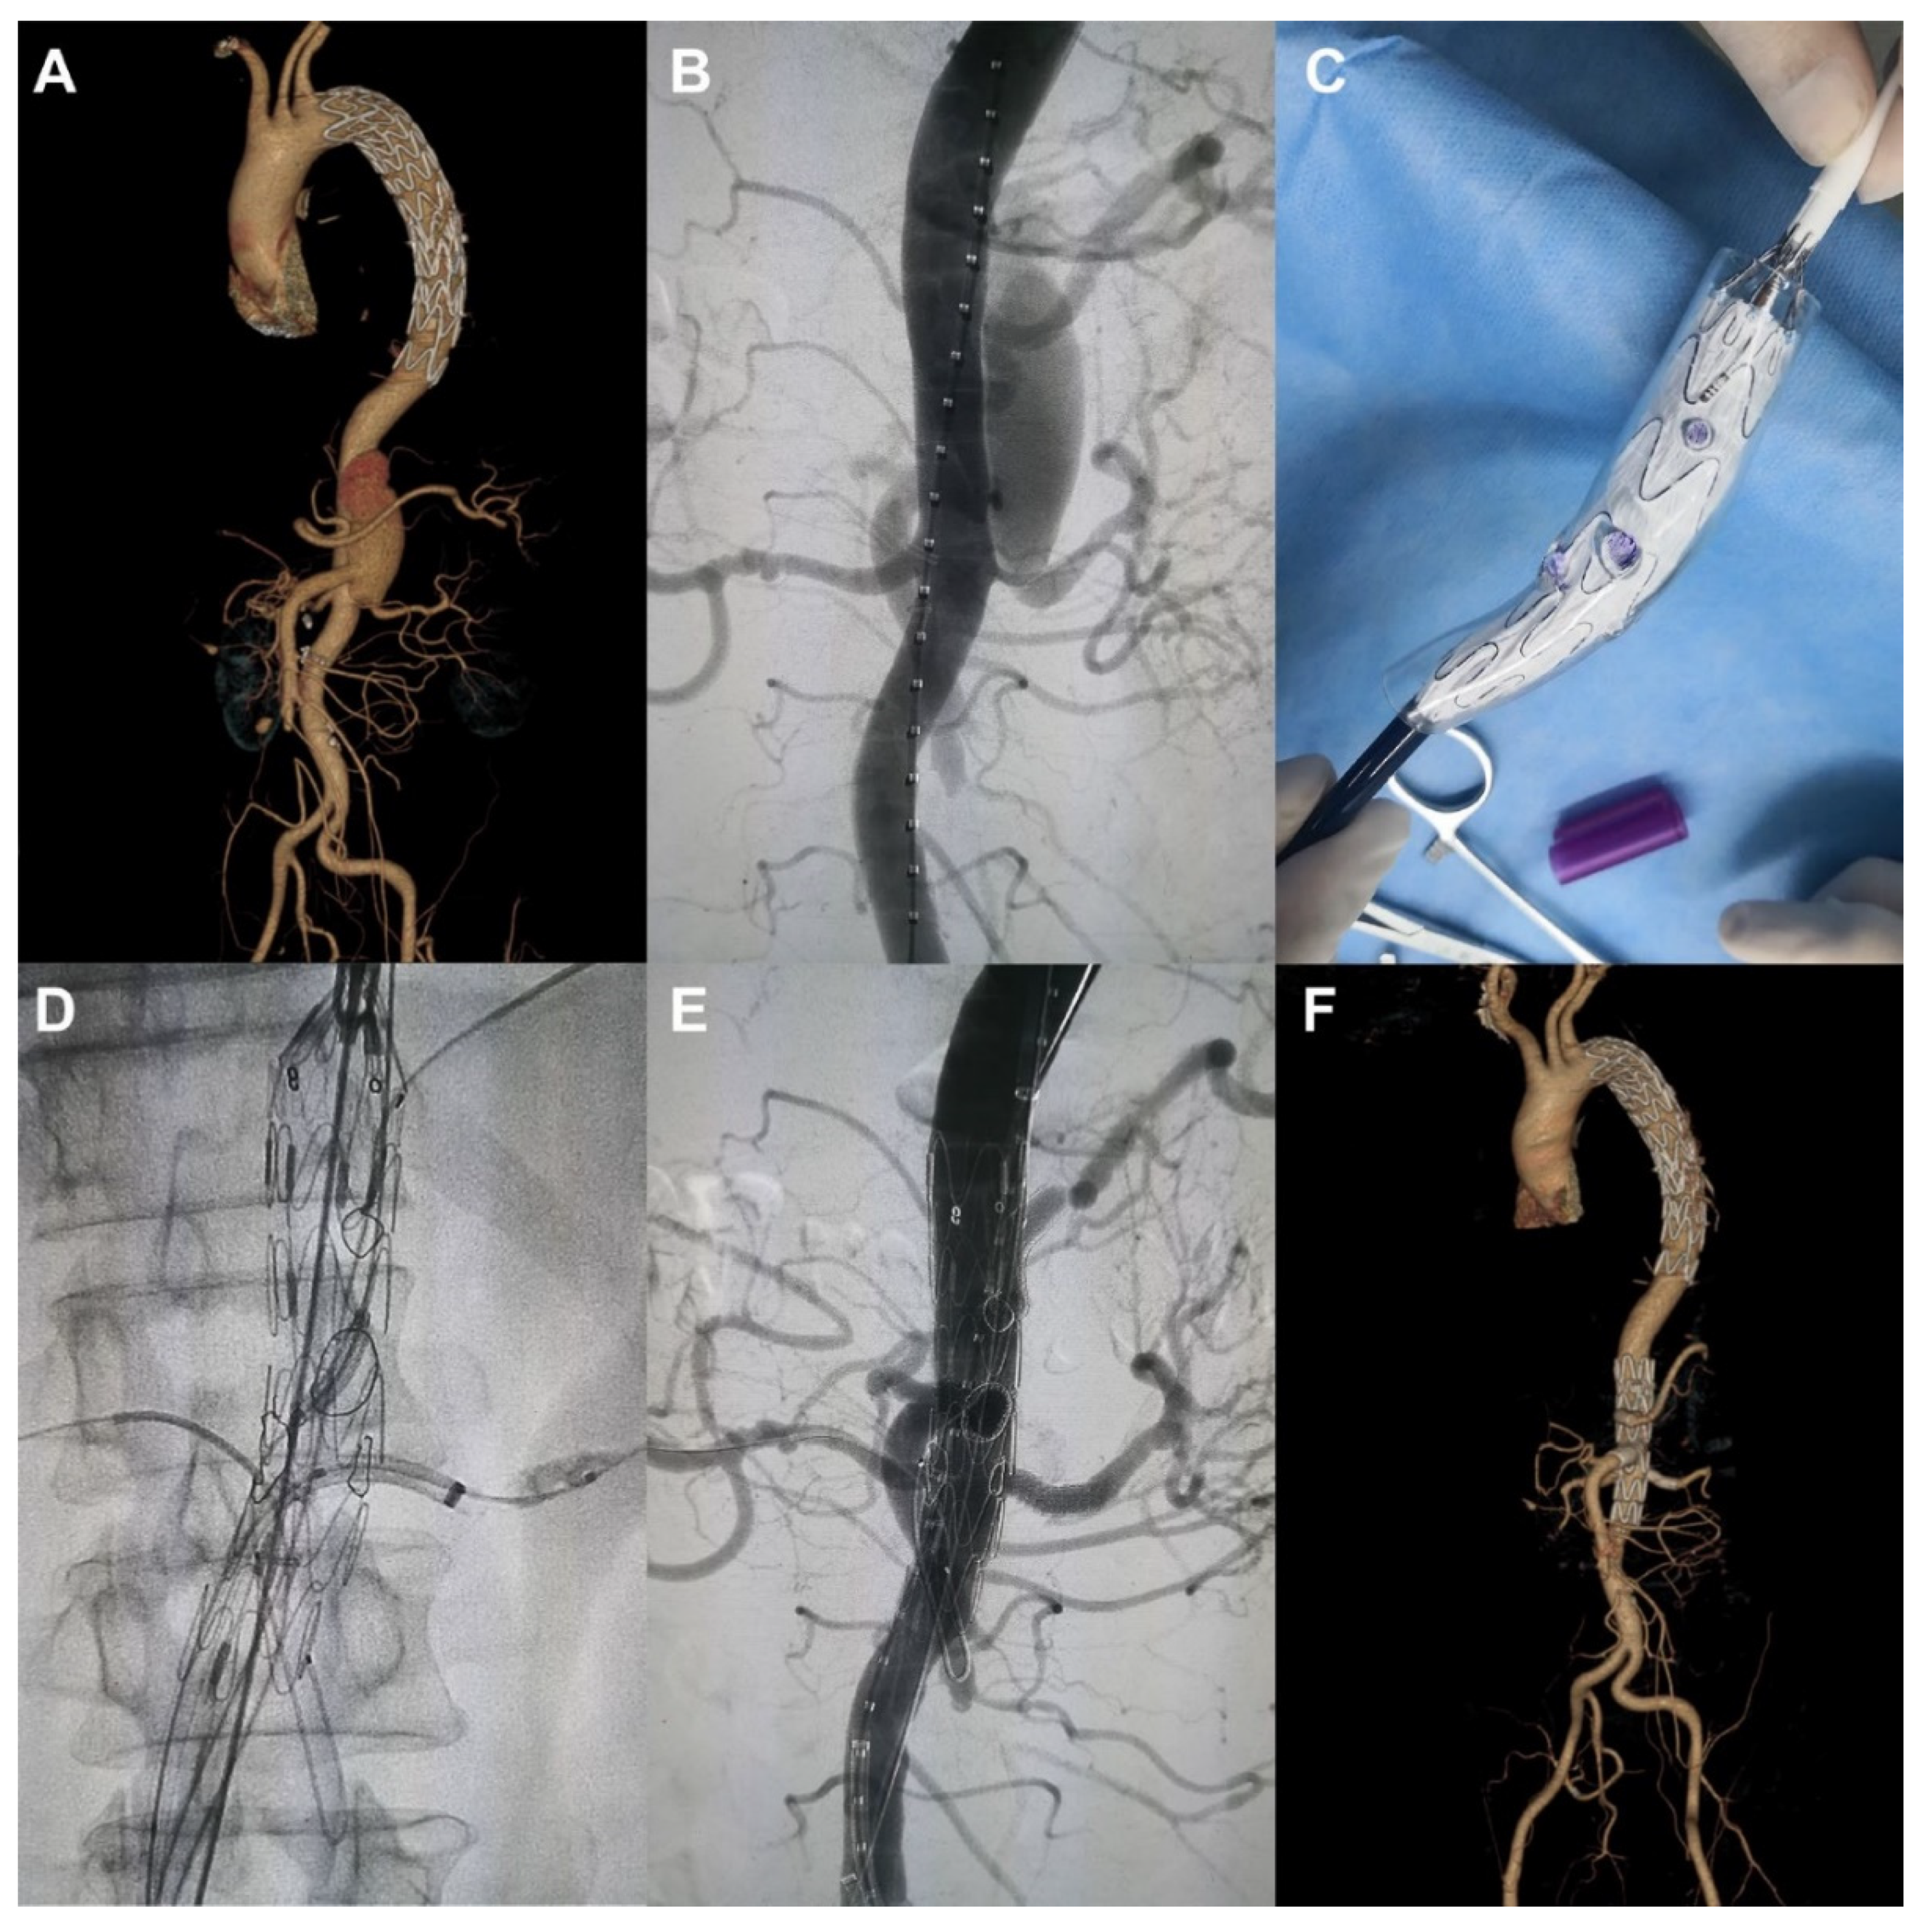

- Huang, J.; Li, G.; Wang, W.; Wu, K.; Le, T. 3D printing guiding stent graft fenestration: A novel technique for fenestration in endovascular aneurysm repair. Vascular 2017, 25, 442–446. [Google Scholar] [CrossRef]

- Mitsuoka, H.; Terai, Y.; Miyano, Y.; Naitou, T.; Tanai, J.; Kawaguchi, S.; Goto, S.; Miura, Y.; Nakai, M.; Yamazaki, F. Preoperative planning for physician-modified endografts using a three-dimensional printer. Ann. Vasc. Dis. 2019, 12, 334–339. [Google Scholar] [CrossRef] [PubMed]

- Rynio, P.; Kazimierczak, A.; Jedrzejczak, T.; Gutowski, P. A 3-dimensional printed aortic arch template to facilitate the creation of physician-modified stent-grafts. J. Endovasc. Ther. 2018, 25, 554–558. [Google Scholar] [CrossRef]

- Tong, Y.H.; Yu, T.; Zhou, M.J.; Liu, C.; Zhou, M.; Jiang, Q.; Liu, C.J.; Li, X.Q.; Liu, Z. Use of 3D printing to guide generation of fenestrations in physian-modified stent-grafts for treatment of thoracoabdominal aortic disease. J. Endovasc. Ther. 2020, 27, L385–L393. [Google Scholar] [CrossRef]